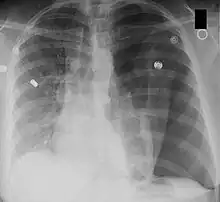

Left-sided tension pneumothorax. Note the area without lung markings which is air in the pleural space. Also note the tracheal and mediastinal shift from the patient's left to right.

Tension pneumothorax

A pneumothorax occurs when air collects in the pleural space around the lungs. Normally, this space has negative pressure to allow the lung to fill. Pressure increases as more air enters this space.[7] The lung collapses, impairing normal breathing. Surrounding structures may also shift. When severe enough to cause these shifts and hypotension, it is called a tension pneumothorax. This is life-threatening. The increased pressure inside the chest can compress the heart and lead to a collapse of the blood vessels that drain to the heart. The veins supplying the heart are compressed, in turn decreasing venous return.[7] With the heart unable to fill, cardiac output drops. Hypotension and shock ensue. If not rapidly treated, it can lead to cardiac arrest and death.[8]

A chest X-ray can rapidly identify a pneumothorax, seen as absence of lung markings. Ultrasound can show the lack of lung sliding. However, imaging should not delay treatment.[8] CT angiography is the standard of diagnosis of pulmonary embolism. Clots appear in the vasculature as filling defects.[18]